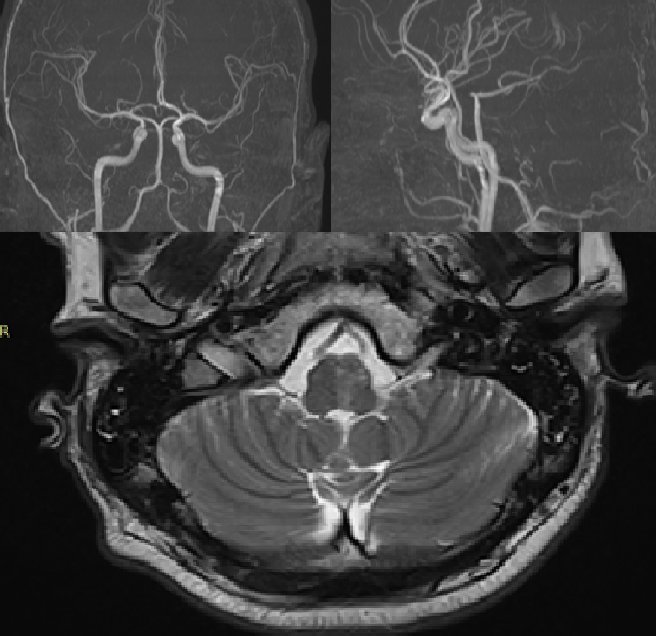

Upon admission, the patient was conscious but presented with cerebellar dysarthria and vestibulo-atactic syndrome. No other focal neurological deficits were detected. Doppler ultrasound of the major neck vessels revealed a dissection of the left vertebral artery. Contrast-enhanced magnetic resonance imaging (MRI) of the brain confirmed a dissection in the V4 segment of the left vertebral artery. No cerebral ischemic foci were identified (Fig. 1).

Fig. 1. Dopplerography of the main vessels of the neck.

On the 5th day of hospitalization in the neurology department, the patient's blood pressure increased to 190/100 mm Hg. He developed numbness in the right limbs, dysphagia, dysarthria, worsening ataxia, left-sided ptosis, and right-sided hemiparesis and hemihypoesthesia. A follow-up MRI of the brain revealed an ischemic focus in the medulla oblongata (Fig. 2).

Fig. 2. MRI examination of the brain.